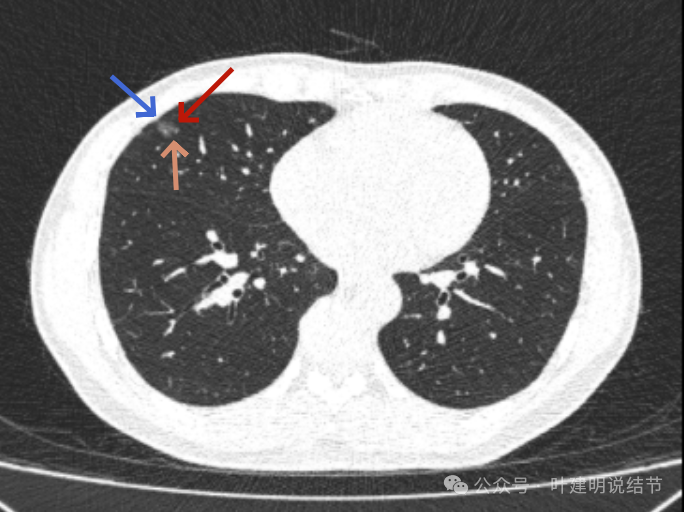

上图是2024年10月的,可惜不是薄层影像,与2023年的可比性差。